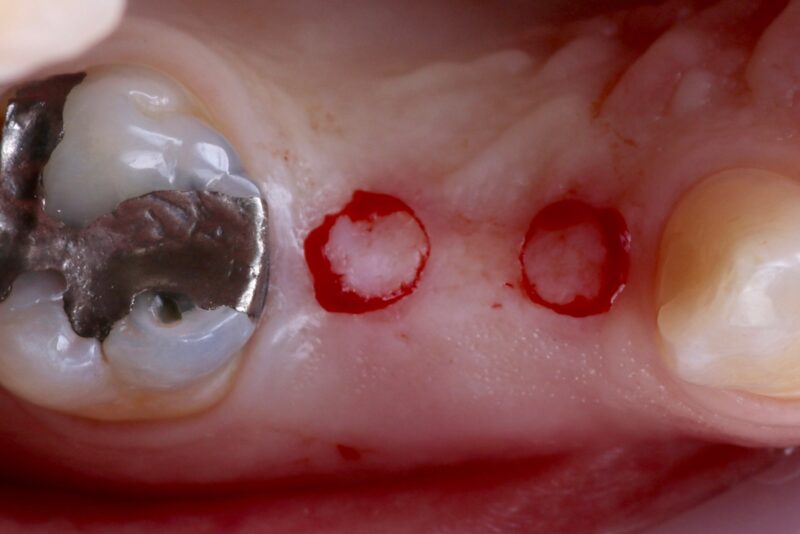

Looking back at a case I did a few years ago, I’ve realized how much my approach has evolved.

I placed two implants in the posterior region using guided surgery. At the time, I chose a tissue punch technique because there was plenty of keratinized tissue, and it felt like the most minimally invasive option. The implants healed well, and the…